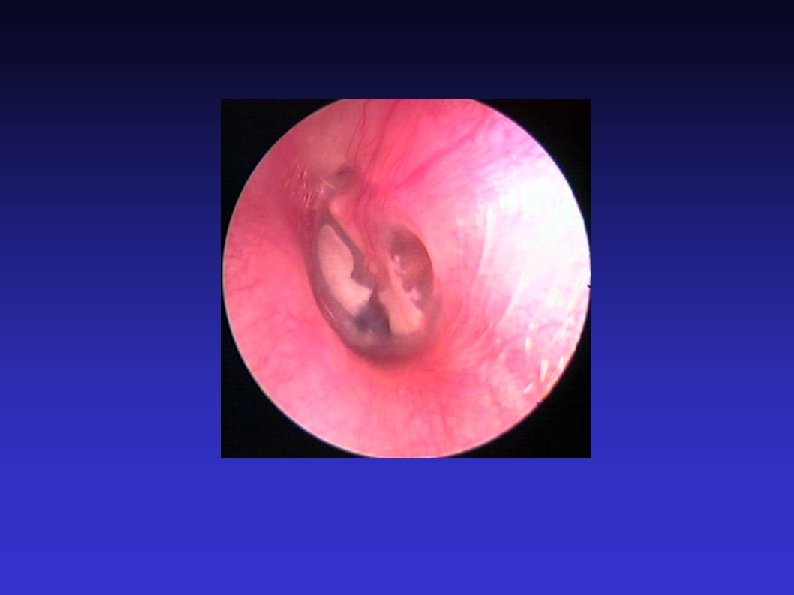

Examination of the Ear 7) Otoscopic examination The lateral process and handle of the malleus lie towards the centre of the tympanic membrane Four quadrants Perforation Central or marginal What can be seen through it Mastoid cavity Dry Wet, inflamed

Examination of the Ear 8) Fistula test A test for ENT doctors! Warn the patient A cholesteatoma has erroded part of a semi-circular canal Pressure in the EAM causes conjugate deviation of the eyes

Examination of the Ear 11) Facial nerve Otoneurological conditions affect the cranial nerves closest to the vestibulocochlear nerve Cholesteatoma Malignant otitis externa (osteomyelitis) Vestibular Schwannoma (formerly acoustic neuroma) Other skull-base tumours